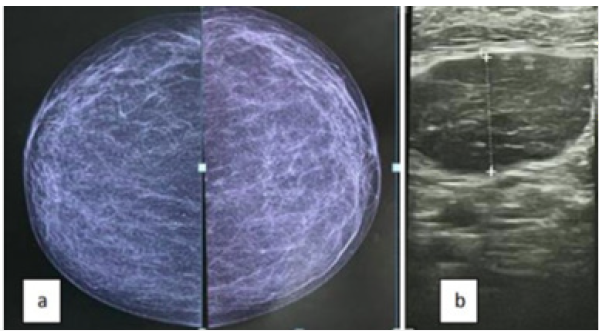

56-year-old women was admitted to our institution in January 2020 to clarify an asymptomatic right axillary lump. She was being treated for chronic hypertension and had no relevant family history. A bilateral mammogram (Figure 2) and a breast ultrasound were normal. Images were reviewed and a needle biopsy was performed. Pathological examination revealed a right axillary metastasis. Immunohistochemical profile with 90 % positivity for estrogen and progesterone receptors, and Ki-67 60 % (Luminal B like). MRI was performed showing no pathological changes. PET-CT, in addition to abnormal uptake in the axillary lesion, showed no pathological FDG uptake. The IHC profile suggests a breast origin. The patient underwent a supero-external quadrantectomy following the decision of the CPR.